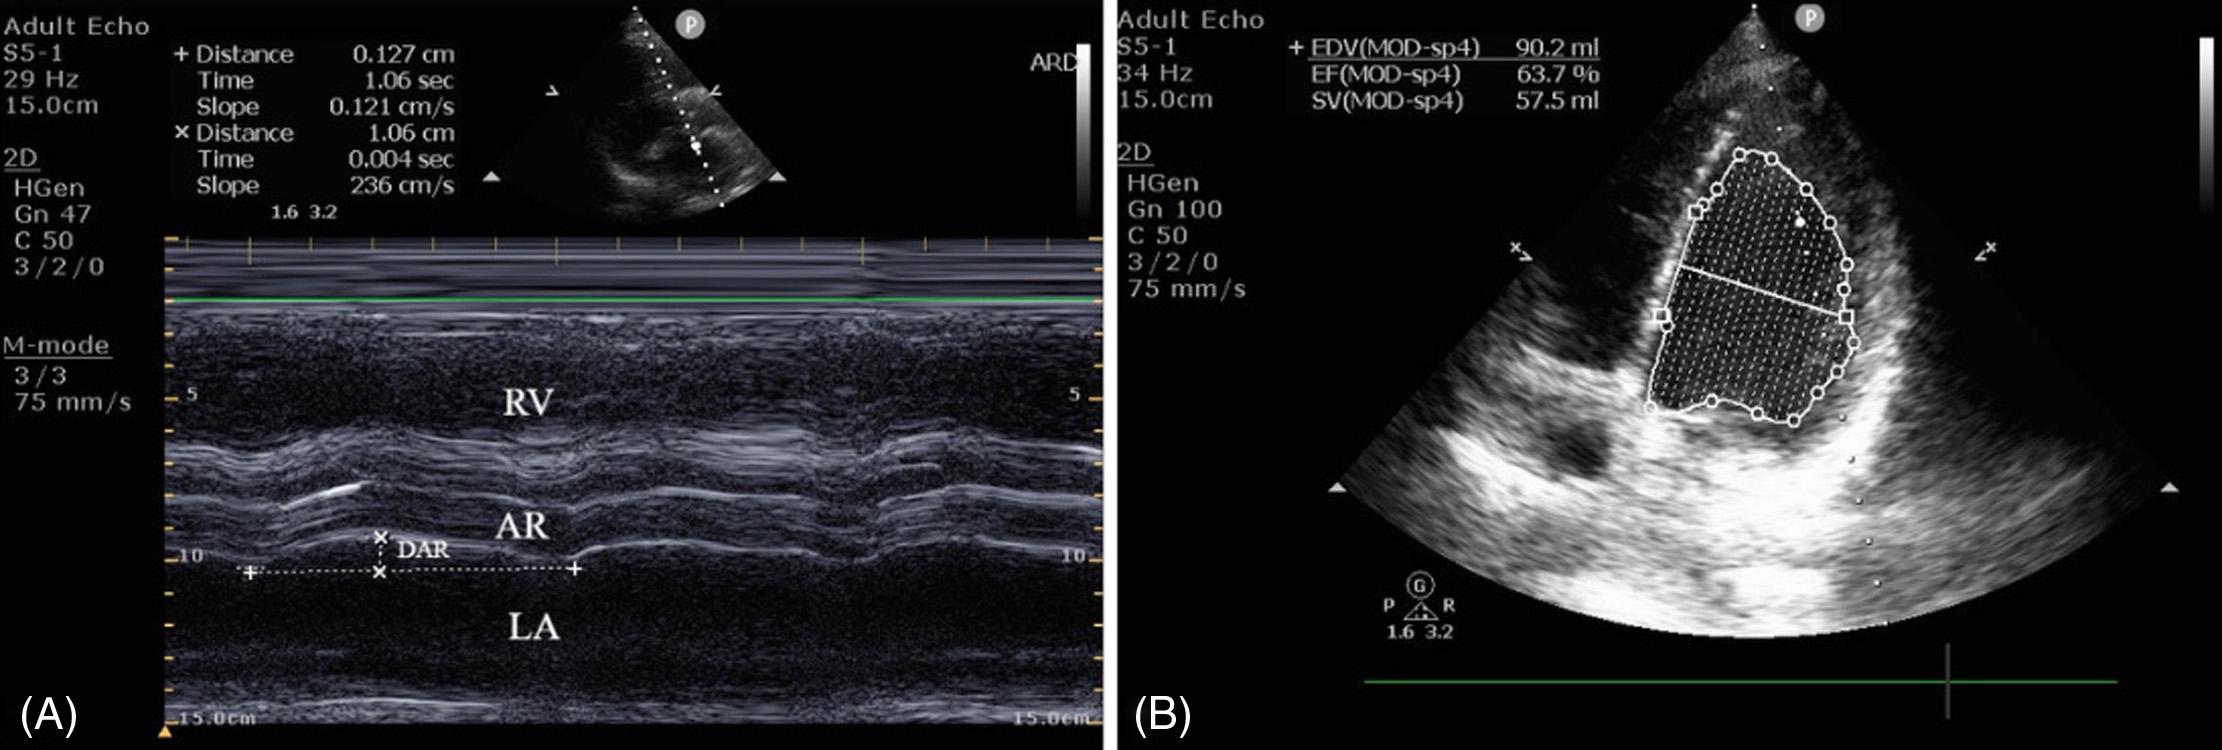

Introduction: Assessingcardiacfunctioniscrucialformanagingacutedyspnea.Inthisstudyweaimed toevaluatedisplacementoftheaorticroot(DAR)asamethodforcalculatingejectionfraction(EF)in patientswithundifferentiateddyspneapresentingtotheemergencydepartment(ED).Theprimary objectivewastocompareEFvaluesobtainedthroughDARwiththemodifiedSimpsonmethod,whichis consideredthecriterionreference,withinanIndianacademicED.

Methods: Weconductedaprospective,cross-sectionalstudyspanningtwoyears(December 2019–December2021).Thestudyenrolled110consecutiveEDpatients ≥18yearsofage,presenting withundifferentiateddyspneaandnormalsinusrhythm.Ultrasound-trainedinvestigatorsmeasuredDAR usingM-modeultrasonography.Experiencedechocardiographers,blindedtoDAR,determinedEF usingthemodifiedSimpsonmethod.StatisticalanalysesincludedtheShapiro-Wilktest,McNemartest, andthereceiveroperatingcharacteristiccurve.

Results: ThemeanDARmeasurementwas0.781centimeters,withanaveragecalculatedEFof54.4%. TheEFcalculatedusingDARdidnotdiffersignificantlyfromEFcalculatedusingthemodifiedSimpson method.ComparativeanalysisrevealedDAR’ssuperiorsensitivity(86.21%)comparedtomitralannular planesystolicexcursion(48.28%)andend-pointseptalseparation(45.45%).TheDARmethodexhibited highaccuracy(areaunderthecurve = 0.958)withacut-offvalue0.706(sensitivity88.7%, specificity93.1%).

Conclusion: Evaluatingdisplacementoftheaorticroottocalculateejectionfractioninundifferentiated dyspneademonstratedhighaccuracy,sensitivity,andagreementwiththemodifiedSimpsonmethod, whichisconsideredthecriterionreference.Itssimplicityandnon-invasivenessmakesitavaluableinitial screeningtoolinemergencysettings,withthepotentialtoreshapecardiacassessmentapproachesand optimizepatientcarepathwaysintheED.[WestJEmergMed.2025;26(2)191–199.]

Assessingcardiacfunction,particularlyejectionfraction (EF),iscrucialformanagingacutedyspnea.1–3 EchocardiographyisthecurrentstandardforcalculatingEF, butdisplacementoftheaorticroot(DAR)hasemerged asapotentialtoolforEFcalculationinpatientswith undifferentiateddyspnea.2,3 TheDARmethodquantifies alterationsinleftventricular(LV)volumethroughoutthe cardiaccycle,providingasurrogatemeasureforestimating EF.3 End-pointseptalseparation(EPSS)measurementisa relativelystraightforwardskillthatanemergencyphysician canacquirewithminimalexperience,evenwhenconfronted withregionalwallmotionabnormalities.4,5 However, measurementofLVend-systolicandend-diastolicdiameters using2DorM-modeechocardiographycanposechallenges totheemergencyphysicianinclinicalpractice.Tracingthe endocardialborderoftheheartinanechocardiogramduring diastoleandsystoleisoftendifficultandtime-consuming, especiallywherethewallispoorlydefined.6–10 Thisapproach providesclinicianswithmultipleoptionsforassessingLV systolicfunction,cateringtovaryinglevelsofexpertiseand clinicalsettings.

throughthemodifiedSimpsonmethod,definedasthe criterionreferencebytheAmericanSocietyof Echocardiography(ASE).9,16 Thesecondaryobjectivewas toidentifythecut-offforDAR,whichcouldpredictLV dysfunctionbasedonEFcalculation.Additionally,we soughttocomparetheEFcalculatedfromDARwiththose obtainedthroughEPSSandMAPSE.ByevaluatingDARin comparisontotheestablishedmethods,weaimedtoprovide insightsintoitspotentialasareliabletoolforEFestimation intheIndiansetting.

Figure1. Theprobeispositionedintheparasternallong-axis view,withthetransducerplacedperpendiculartothechestwallat thethirdorfourthintercostalspace,justtotheleftofthesternum, andtheprobemarker(blackstar)directedtowardsthepatient’s rightshoulder.